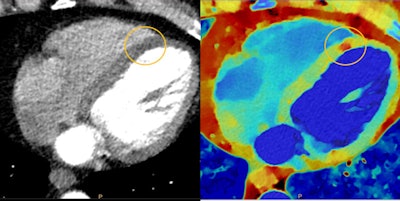

Myocardial perfusion defects are difficult to visualize on conventional CT (left) due to beam-hardening artifacts, but they are visible on spectral CT (right). Image courtesy of Philips Healthcare.

Myocardial perfusion defects are difficult to visualize on conventional CT (left) due to beam-hardening artifacts, but they are visible on spectral CT (right). Image courtesy of Philips Healthcare.Philips tackled these issues head-on with Spectral CT 7500. Launched in May 2021, the scanner is designed to make spectral CT easy enough to perform for routine daily use. The system acquires 8 cm of data per gantry rotation, which eliminates the need for image stitching. Philips also reduced the number of mouse clicks required to generate spectral images.

Radiation dose was addressed with an enhanced detector and imaging chain that allows single-pass image acquisition at 100 kVp, compared with 120 kVp for the previous generation of Philips spectral CT scanners.

Spectral CT 7500 can operate in spectral mode for a variety of clinical applications, including cardiology, oncology, neurology, and trauma. The company believes that spectral CT can save healthcare costs by eliminating the need to perform follow-up studies after an inconclusive exam.